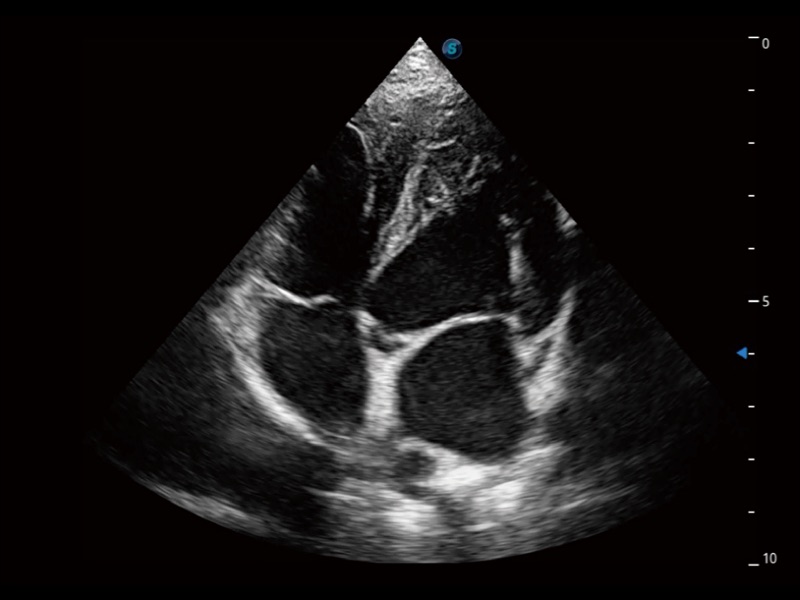

通过360度任意调节3条M型取样线,在同一心动周期上观察心脏不同位置的运动曲线,得到准确的心功能测量数据,有效评估心肌运动及左心室功能。

实时用颜色表示心肌组织运动,观察和定量组织的运动情况,对快速检测与评估心肌的灌注和活性、电传导及心肌收缩和舒张功能等均能提供重要的诊断信息。

当心脏测量结果超出正常范围时,可实时预警提示动物医生,减少疾病漏诊概率。